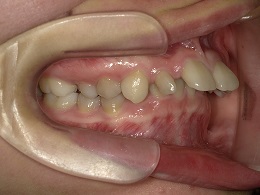

治療前右側

治療前上顎